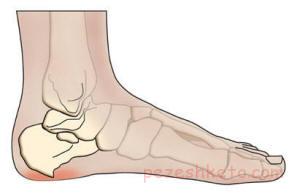

خار پاشنه پا عبارت است از به وجود آمدن یك زائده استخوانی در پاشنه پا كه باعث درد و مشكل در راه رفتن می شود.

خار پاشنه پا